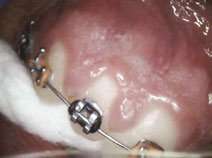

Gingival hypertrophy caused by orthodontic positioning and poor oral hygiene as well as overlying operculum are common problems during orthodontic therapy.[7] Drug-induced hyperplasia presents another challenge for some orthodontic patients.[7] Additionally, orthodontic devices attract bacteria and thus exacerbate the inflammation; periodontal disease often worsens in adolescents with fixed orthodontic hardware.[7] Figures 7-8 demonstrate completely bloodless CO2 laser gingivectomy around the mandibular incisors in the orthodontic patient. CO2 laser gingivectomies, such as the ones presented in Figures 7-8, help to improve the esthetics and oral health; they also allow for more ideal bracket placement and quicker treatment with fewer appointments.